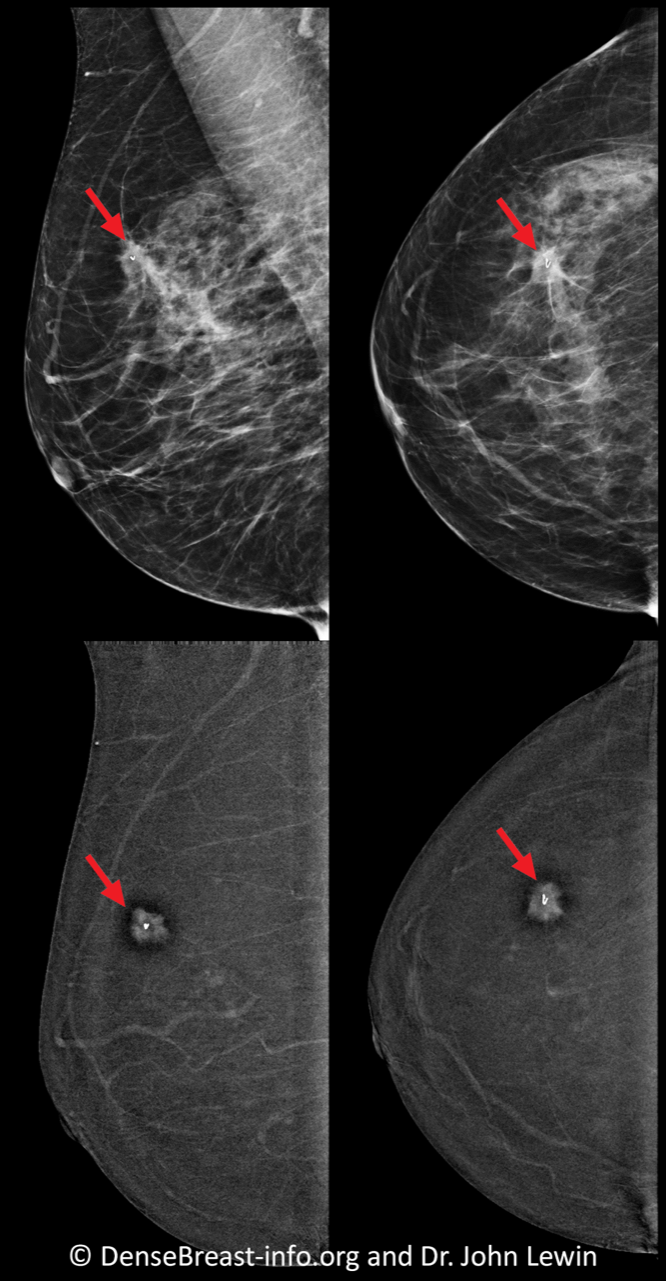

Per la CEM, il posizionamento e la compressione del seno sono gli stessi di una mammografia digitale standard. Per ogni seno si ottengono due esposizioni mammografiche (immagini) in ciascuna delle due posizioni, per un totale di quattro immagini per seno (otto immagini in totale per un tipico esame CEM). Un’esposizione utilizza raggi X a bassa energia e assomiglia a una mammografia standard. La seconda esposizione utilizza raggi X ad alta energia che vengono assorbiti principalmente dallo iodio nell’agente di contrasto. Le immagini a bassa e alta energia vengono elaborate dal software per creare un’immagine “solo iodio” che mostra solo i risultati che “migliorano”. I tumori in genere migliorano più del tessuto normale e quindi appaiono di un bianco più brillante, mentre il tessuto normale circostante di solito appare scuro (Fig. CEM-1). Per questo motivo, la maggior parte dei tumori è più facile da vedere sulle immagini “solo iodio” che su una mammografia standard o una tomosintesi. Il radiologo esaminerà le immagini “solo iodio” insieme alle immagini a bassa energia [3].

Figura CEM-1. Mammografia con mezzo di contrasto. In alto: viste obliqua mediolaterale (MLO) e craniocaudale (CC) di una mammografia digitale standard con cancro (frecce rosse), che è difficile da vedere, anche per un radiologo esperto. In basso, immagini “solo iodio” nello stesso paziente, è chiaramente visibile l’aumento di massa dovuto al cancro invasivo (frecce).